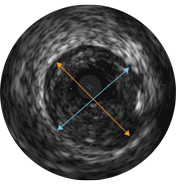

Vessel diameters may be determined at proximal and distal reference sites by obtaining lumen diameters, mid-wall diameters (halfway between lumen and vessel), or vessel diameters, in order of increasing aggressiveness.

If maximum and minimum diameters are used, measurements should bisect the geometric center of the vessel rather than the center of the IVUS catheter.